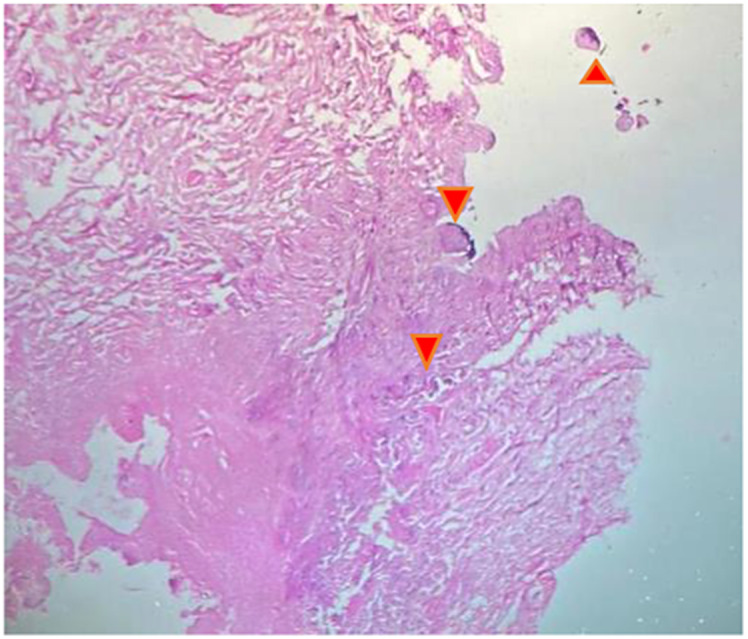

Case presentation: We present the case of a 60-year-old woman, with a history of renal lithiasis, hypertension, and end-stage renal disease on hemodialysis complicated by hyperparathyroidism and aortic valve replacement. She developed extensive necrotic lesions on both lower limbs and upper extremities, prompting a diagnosis of calciphylaxis. Radiographic and biopsy findings supported the diagnosis, revealing characteristic calcifications. Treatment involved antibiotics, oral thiosulfate, daily hemodialysis, hyperbaric oxygen therapy, and discontinuation of calcium and alfacalcidol, with alendronate initiation. Unfortunately, despite these interventions, the patient experienced a rapid clinical decline, developing septic shock necessitating bilateral leg amputations. Regrettably, she succumbed to the disease 10 days later.